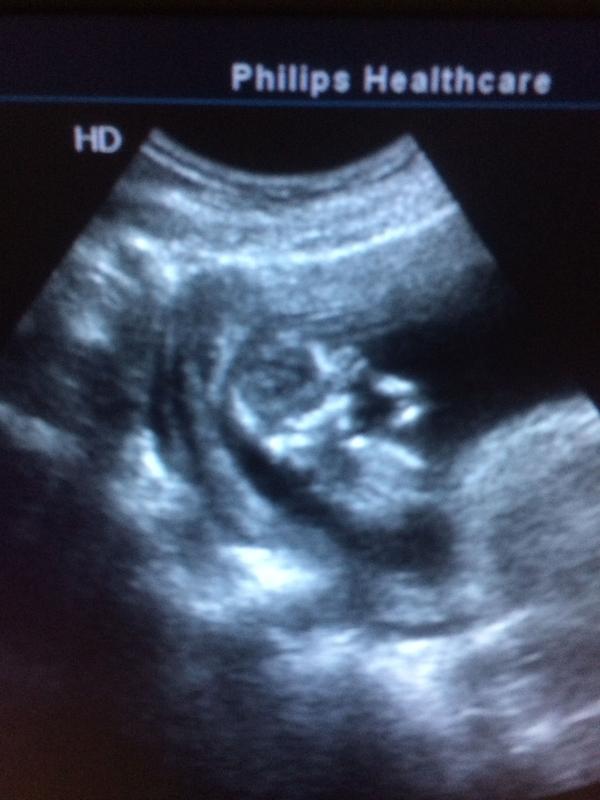

Вот такие мы малыши)) во всю дрыгает ручками и ножками)))13 неделек💕